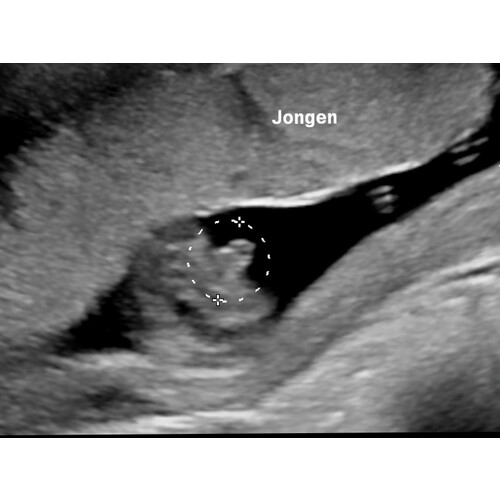

Jongen

Precies vanaf de onderkant